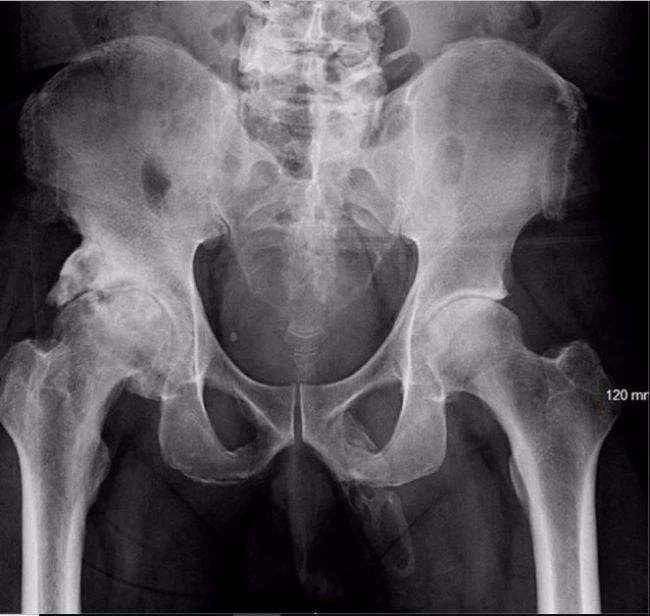

有时,身体里的骨头会长在不该长的位置上。一个63岁的男人就遇到了这种情况,但位置有点儿尴尬——骨头长在了阴茎上。据发表在《泌尿外科报告》九月刊上的病例,这个男人最初是因为跌倒而接受盆腔X光检查的,医生却发现他的整个阴茎轴上都有骨化的现象。换句话说,他的阴茎正在变成骨头。

2019年度十大奇葩病例回顾375 / 作者:UFO爱好者 / 帖子ID:83031

他之后被诊断为患有“阴茎骨化病”,这种情况十分罕见,目前为止全世界只有不到40例报告。而当钙盐沉积在软组织时骨化就会发生,引起骨质的形成。